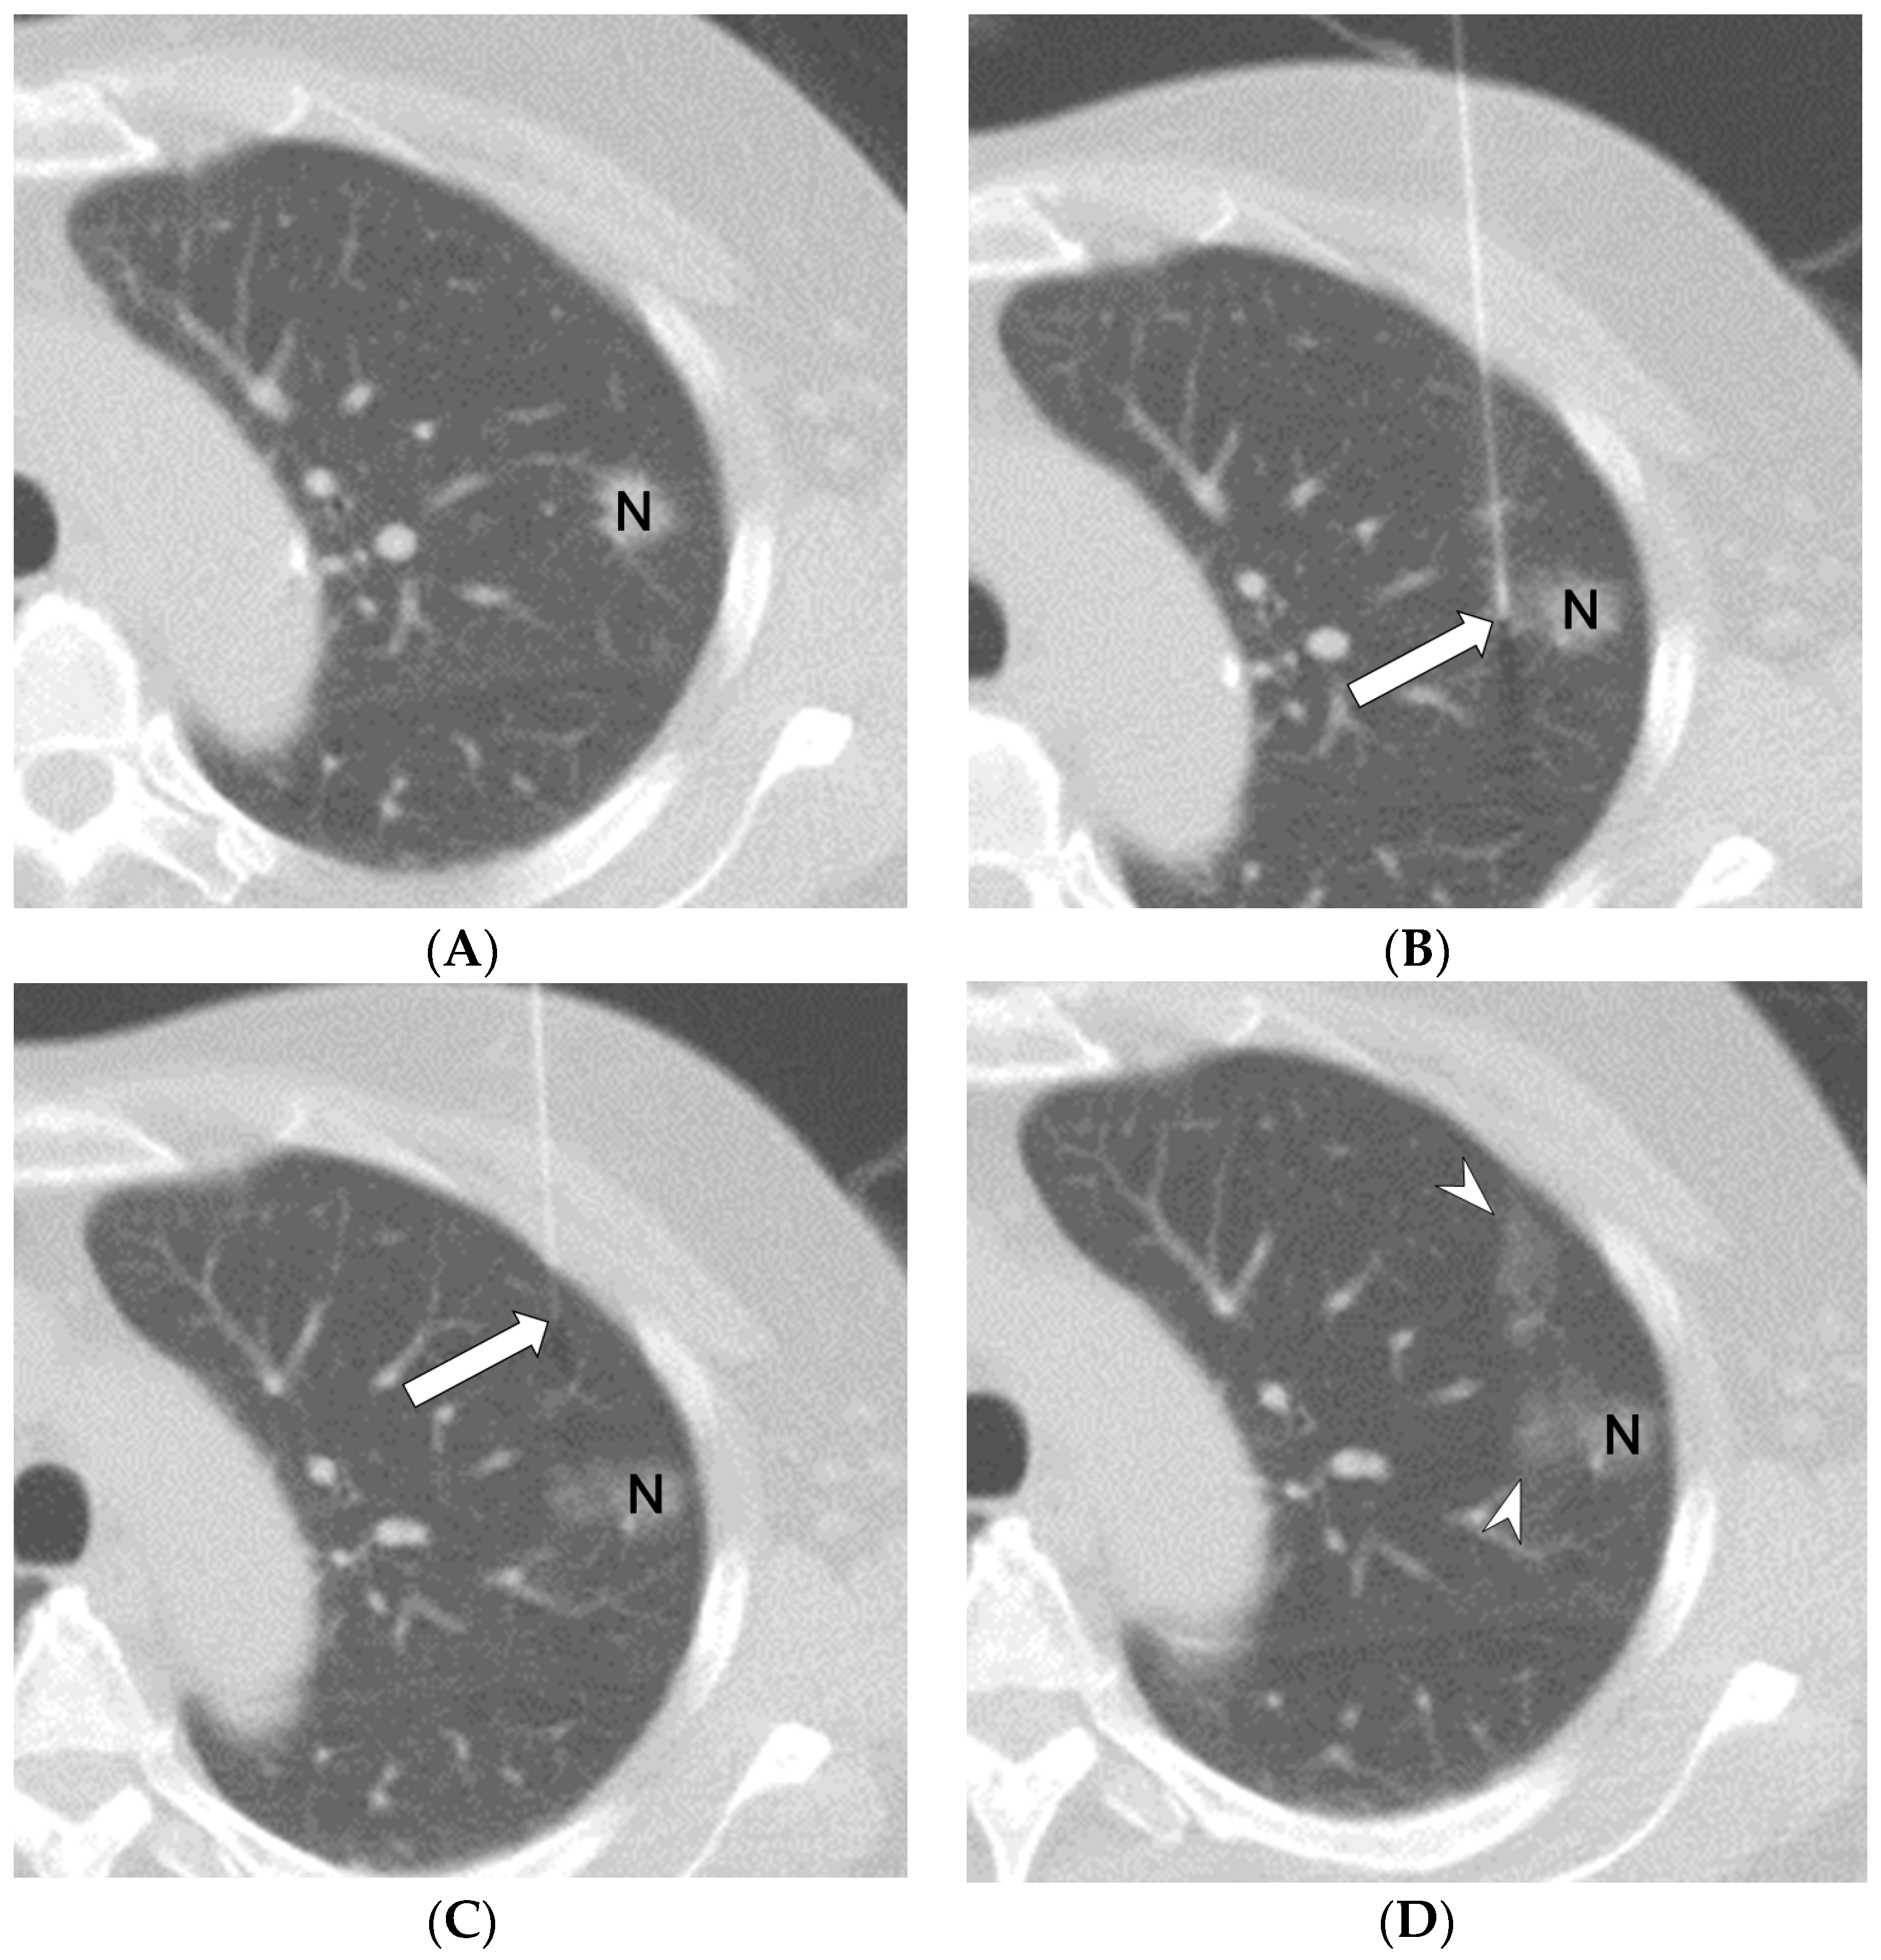

2.2. Methods for CT-Guided Localization with PBV Dye

2.3. Experimental Design and Methods

2.4. Definition of General Data